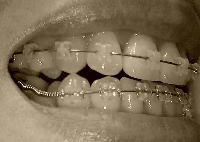

左側

beforeL.jpg 矯正前

060908h.jpg 9月8日

061006d.jpg 今日